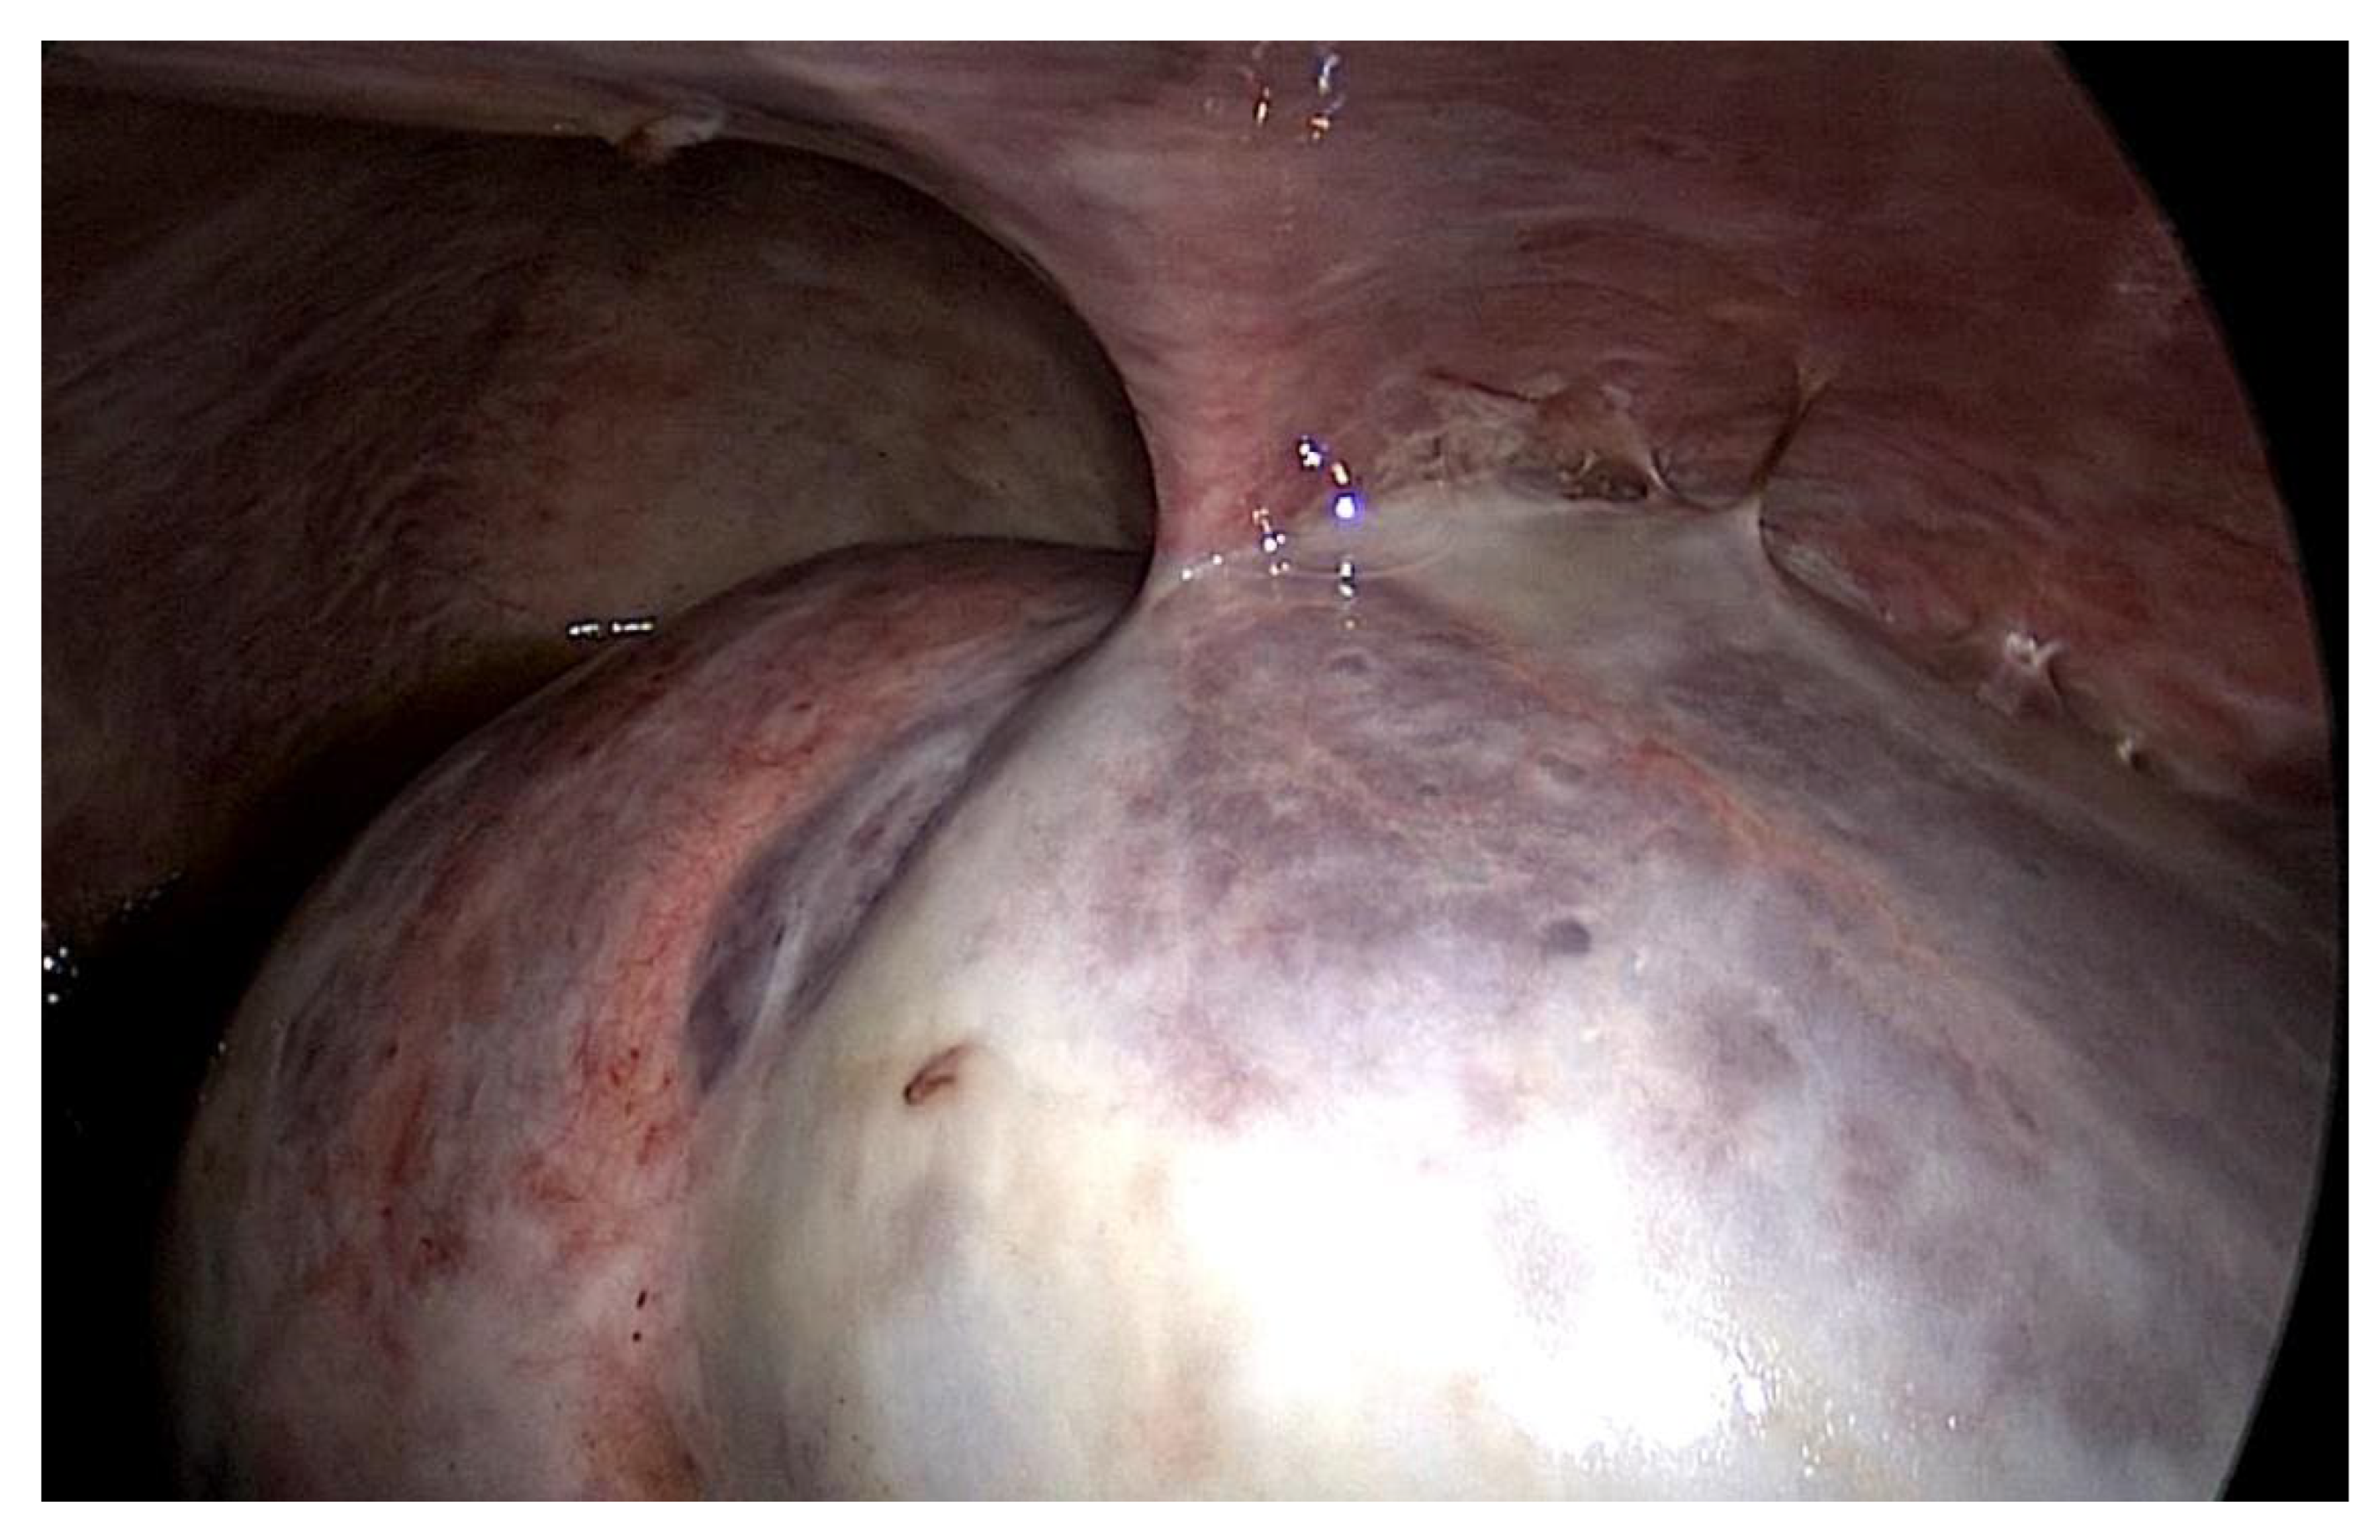

The first patient was a 25 year old woman with lupus nephritis who had undergone PD for 10 years. The PD history of the patient was associated with three episodes of peritonitis (including Mycobacterium tuberculosis, Enterococcus faecalis and Staphylococcus aureus infections, the last of which was 6 years before presentation) and negative ultrafiltration for several months requiring four hypertonic exchanges daily (2X 1.36% and 2X 3.86% Dianeal PD Solution (Baxter International)) to control overhydration. For several months, the patient was suffering from metrorrhagia and bloody effluent for several days. During hospitalization, the effluent became notably hemorrhagic with acute anemia. Emergency surgery was performed revealing hemoperitoneum due to an adnexal pathology. Intraoperatively, we found extensive peritoneal fibrosis encapsulating the small bowel loops and the organs located in the pelvis in a “cocoon” (Figure 1). Furthermore, there was significant bleeding from the site where the right adnexa should have been located and the right fallopian tube and right ovary could not be identified. A visceral “block” representing the right adnexa was dissected and isolated with great difficulty, which was resected to stop the source of the intraperitoneal hemorrhage. A final diagnosis of EPS was confirmed by the pathologist. The immediate and late postoperative outcomes were good, without any surgical complications; however, the patient subsequently died 6 months later due to a hemorrhagic stroke.

The second patient was a 44 year old woman who had undergone PD for 11 years. The patient was referred for nausea, vomiting and metrorrhagia accompanied by a palpable mass in the lower abdomen. A CT scan revealed the presence of an abdominopelvic tumor measuring 12 cm in diameter, suggestive of a uterine fibroid causing the compression of the rectum. A hemostatic curettage was performed in an attempt to postpone surgery, which proved unsuccessful. Then, laparotomy and a definitive transfer to hemodialysis treatment was decided. The intraoperative macroscopic appearance of the parietal and visceral peritoneum revealed only some areas of peritoneal fibrosis, except for the pelvic peritoneum, which showed extensive fibrosis (Figure 2). The fibromatous uterus was encapsulated in a pelvic “cocoon”, and the rectosigmoid junction adhered to this “pelvic block”.

Figure 1. Intraoperative finding: thickened peritoneum.

Figure 2. Intraoperative finding: thickened peritoneum, ascites.